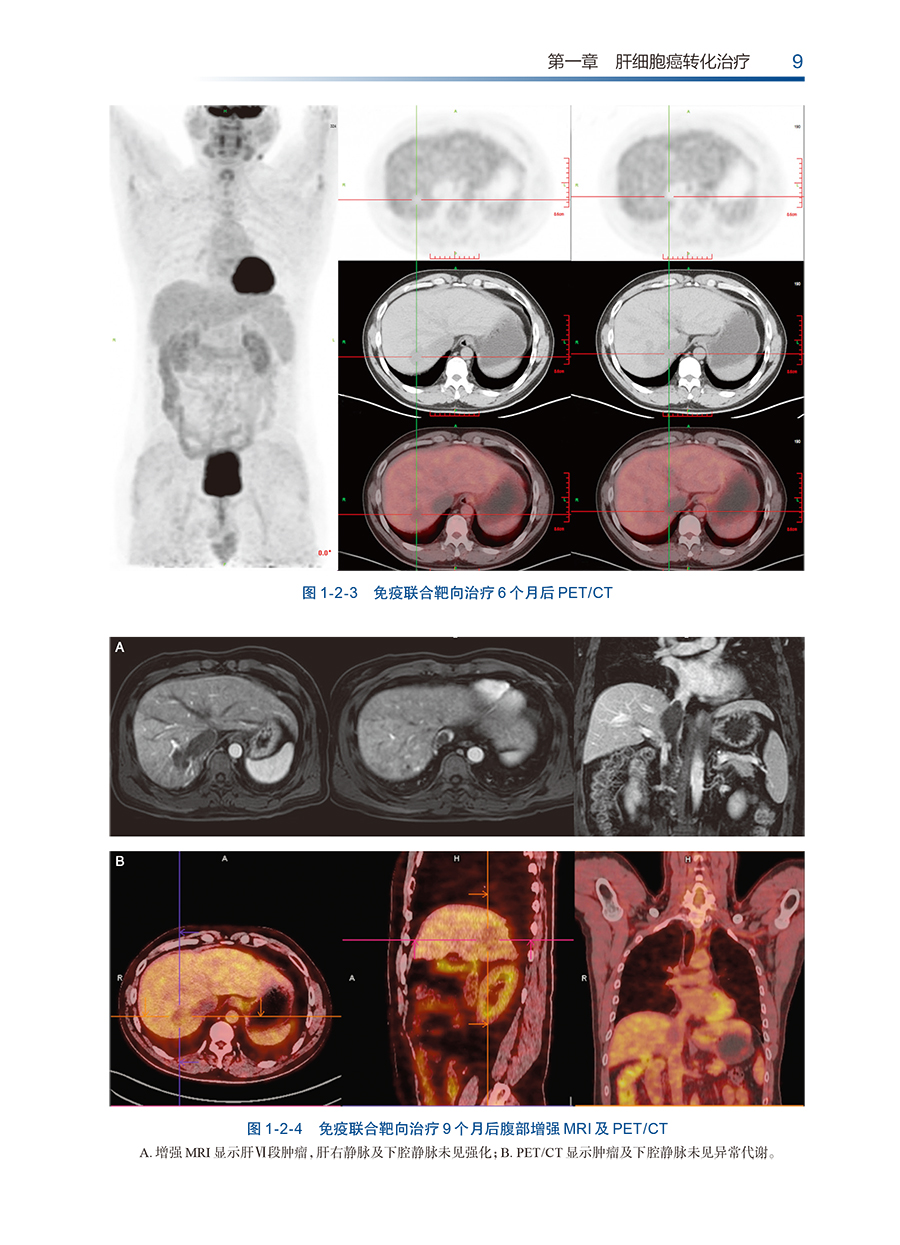

本专著主要包括5个主题,读者对象为肝胆外科医生、肿瘤内科的各年资医生。具体如下:【1】肝细胞癌转化序贯外科治疗:主要内容为晚期原发性肝癌(特指CNLC-Ⅲ期以上或巴塞罗那分期C期以上)患者或初诊时残肝体积不足的患者,接受免疫联合治疗以达到转化效果,再次获得手术指征,并接受包括同种异体肝脏移植或肝脏切除术在内的外科手术以达到肿瘤根治的方案介绍与示例详解。【2】肝细胞癌新辅助治疗:主要内容为对初诊时具备手术指征但临床判断为适宜先行新辅助治疗的肝细胞癌患者,因为新辅助治疗可使得患者远期预后更佳,并且手术更加简单可行。本部分主要涉及到对于新辅助治疗的指征,判断患者新辅助治疗深度与手术时机选取的案例。【3】难治性复发肝癌的免疫联合治疗:主要包括外科或局部治疗术后肝内出现多个复发病灶且复发病灶的数量≥3个;肝内复发病灶累及主要的血管,如侵及肝静脉、门静脉或血管内形成癌栓;出现肝外扩散及远隔转移如肺、骨、脑转移等;出现腹腔内多发淋巴结转移;侵犯肝脏邻近组织及器官或腹腔种植性转移。该方案可控制肿瘤进展并为患者争取手术根治性切除机会,大大提高了患者的生存时间,展示了一种新型治疗模式。【4】其他肝胆系统肿瘤的免疫联合治疗探索:本部分对于包括肝内胆管细胞癌、胆囊癌在内的肝胆系统其他肿瘤性疾病接受免疫联合治疗以达到转化或新辅助治疗效果为目的的治疗进行了探索,并对典型案例进行报道。【5】免疫联合治疗方案的全程管理:因免疫联合治疗方案需要全程管理患者,在本主题中,除了序贯外科治疗方案牵涉的要点外,额外增加免疫联合治疗过程中多个细节问题的处理。如不良反应的监测与处理,耐药或进展的局部叠加治疗与药物联合方案的更换,难治性复发肝癌的免疫联合治疗要点等方面的案例解析。